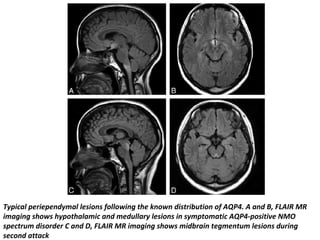

Typical periependymal lesions following the known distribution of AQP4. A and B, FLAIR MR

imaging shows hypothalamic and medullary lesions in symptomatic AQP4-positive NMO

spectrum disorder C and D, FLAIR MR imaging shows midbrain tegmentum lesions during

second attack